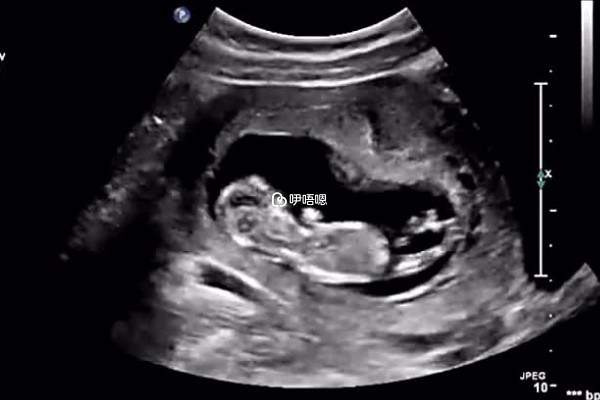

T卵P懷,A卵B懷等都是如今一種試管嬰兒的方式,是指女同性戀中兩人,將一個人的卵子在體外做胚胎培養,然後移植到另一個人的肚子裡,另一方來懷孕,這樣兩個人在孕育的過程中都有參與感,孩子也是兩個人的。

現目前女性同性戀群體想要做試管嬰兒,在國內是無法達到,國內做試管嬰兒的要求比較嚴格,必須提供結婚證,以及不孕證明,但是可以去國外做試管嬰兒,大多數國外的法律都是允許單身女性、同性戀做試管的,比如俄羅斯、美國、泰國等國家都是可以的,女同做試管可以選擇這些方式: